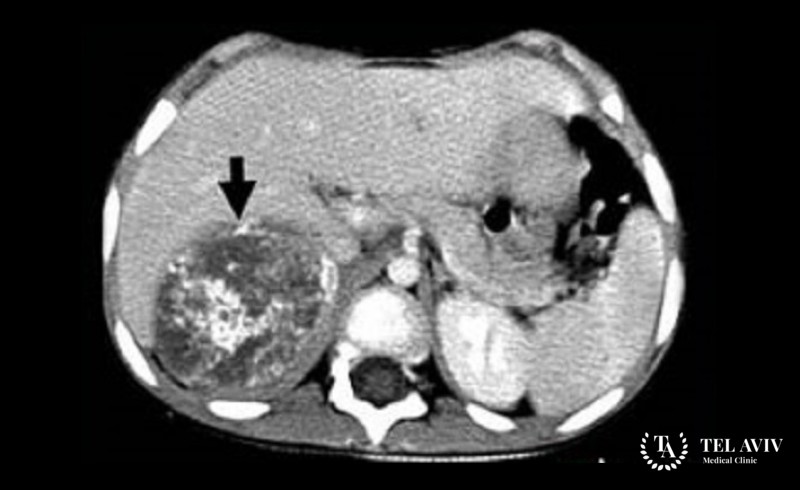

Нейробластома надпочечника

Метастазы, повреждающие костный мозг, стимулируют развитие тромбоцитопении, анемии. Характерная дислокация патологии – мозговое вещество надпочечника.

• Компьютерная томография;